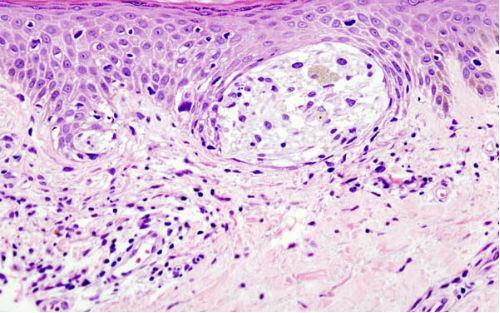

黑色素瘤是一种最致命的皮肤癌形式,晚期黑色素瘤患者只有20%的机会在确诊后存活5年。在过去的几年里,多个黑色素瘤靶向疗法获得批准,但接受这些药物的患者都最终复发,变得对这些治疗方案耐药。

尽管多个因素可以导致年龄相关的癌症发病率增长,Weeraratna实验室第一次精确描绘出了发生于肿瘤细胞微环境中的年龄相关改变。存在于皮肤中的真皮成纤维细胞帮助了皮肤从损伤中恢复过来,可以促成黑色素瘤细胞生长和侵袭。研究人员利用来自年龄在25-35岁之间健康捐献者和年龄在55-65岁之间捐献者的真皮成纤维细胞,了解了造成衰老细胞群体中黑色素瘤进展差异的因素。